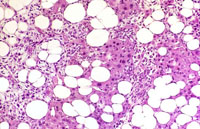

An Ito cell tumor that has replaced much of the normal hepatic parenchyma without distorting the normal contour of the liver; higher magnification shows fat-filled and stellate cells in the hepatic sinusoids.

The proliferating stellate cells have a myxomatous appearance in some areas and have caused atrophy of hepatic cords.